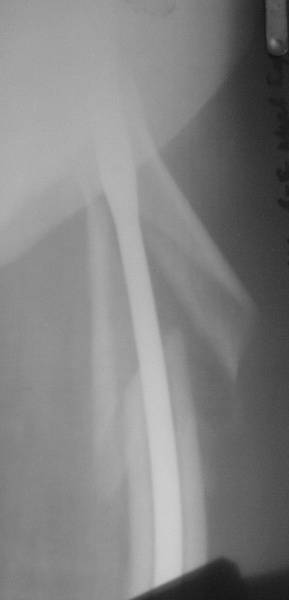

Нашел в архиве наш проблемный остесинтез  на таком-же штифте с  варусным

смещением проксимального отломка, который ,правда, успешно

консолидировался в срок.